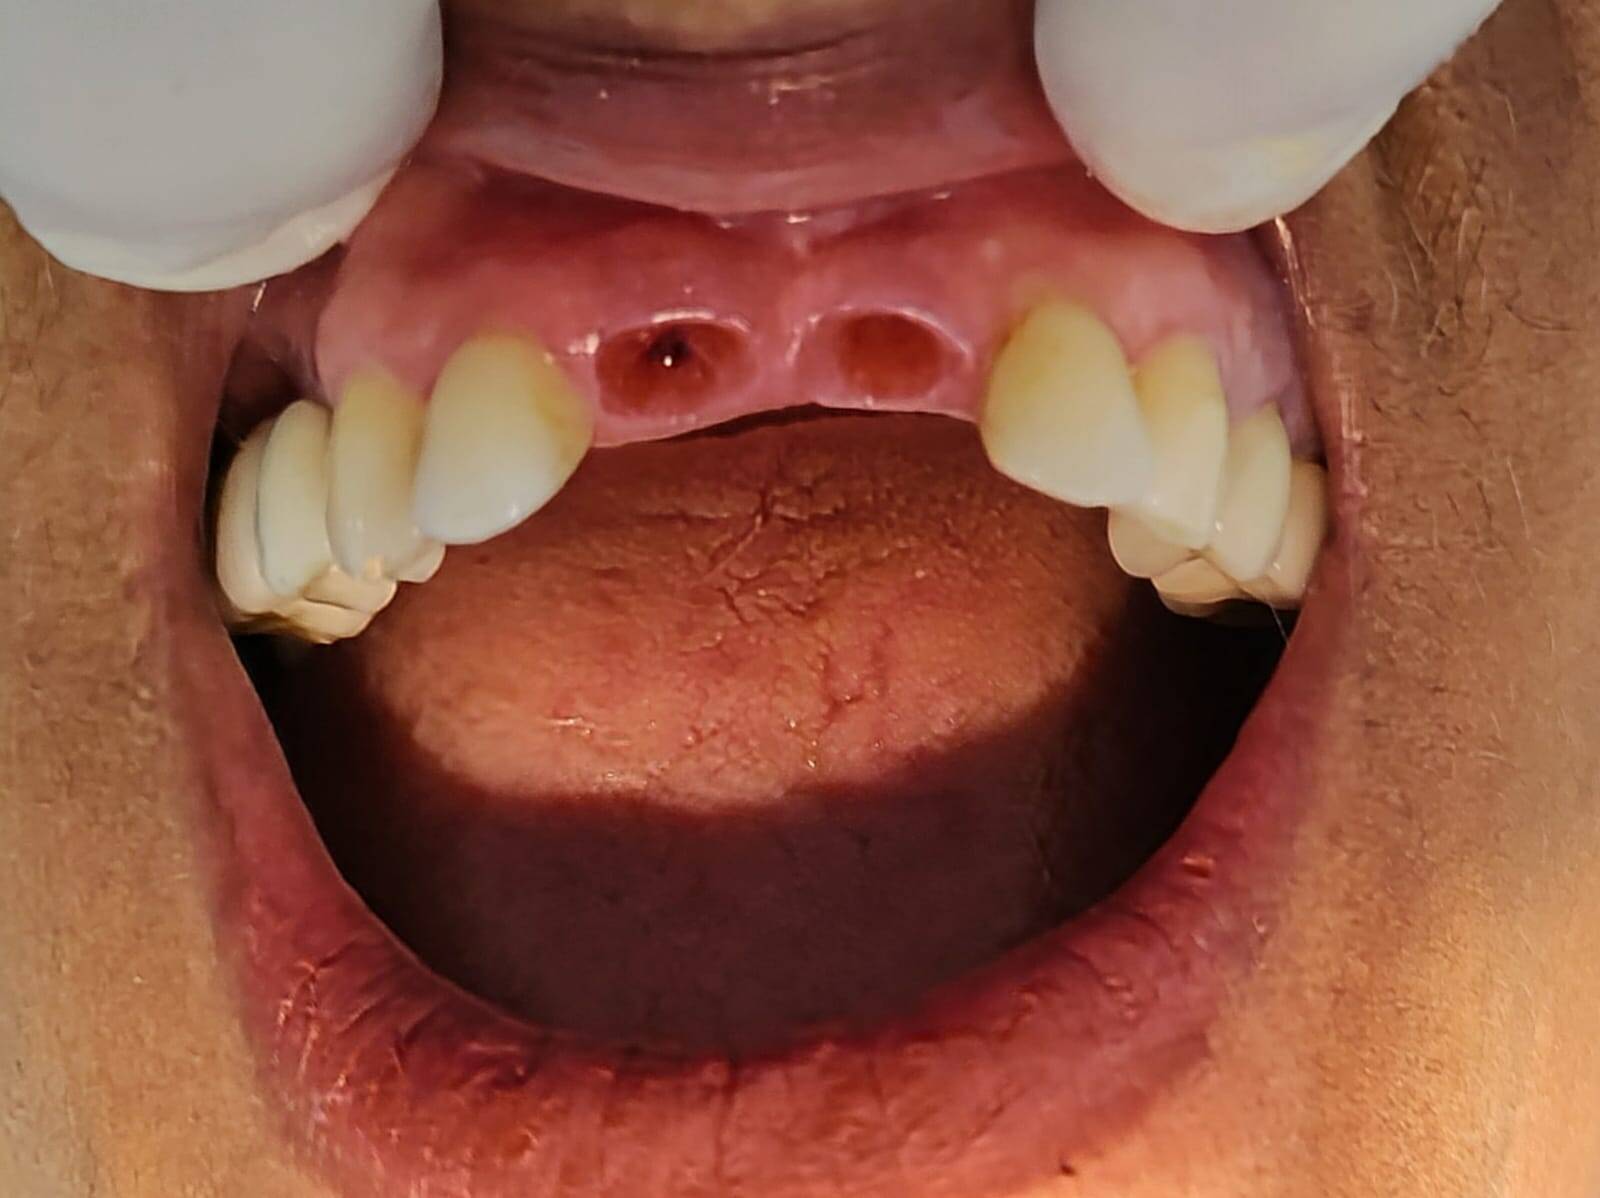

PRIMEIRO CASO REALIZAÇÃO DE IMPLANTE E PRÓTESE SOBRE IMPLANTE DENTES 11 E 21.